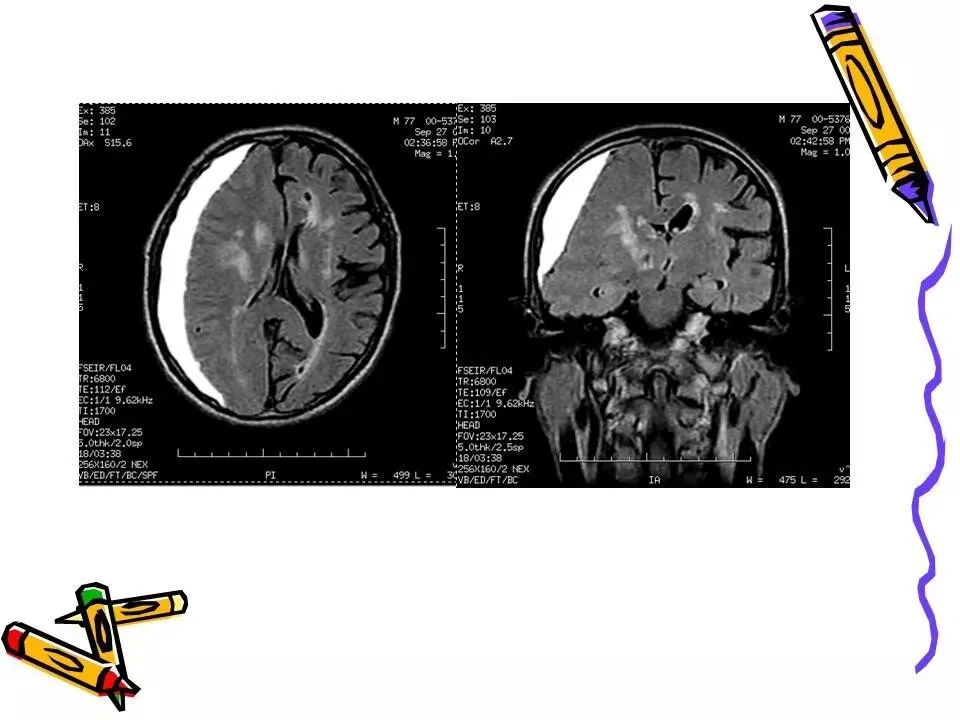

>常见颅脑外伤CT诊断(PPT)

常见颅脑外伤CT诊断(PPT)